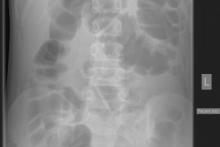

Przypadek 4: 11-letni chłopiec z napadowymi bólami brzucha od 3 tygodni, z wielokrotnymi wymiotami. Pacjent ani rodzice nie potrafili określić kiedy było ostatnie wypróżnienie. Podejrzenie niedrożności przewodu pokarmowego.

Rozpoznanie: Liczne poziomy płynu w dystalnych pętlach jelita cienkiego oraz w miernie rozdętym jelicie grubym do wysokości zstępnicy, brak powietrza w rzucie odbytnicy - cechy niedrożności. Bez cech perforacji.